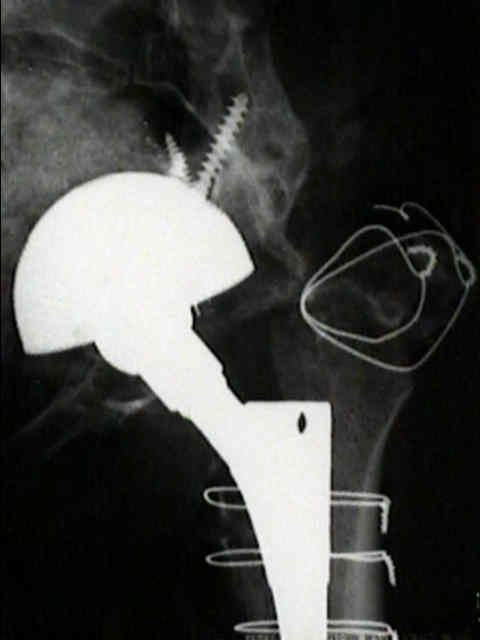

Loosening of Cemented Acetablar Components

(cemented acetabular component)

definite loosening

- migration of component of more than 5 mm;

- crack in cement mantle;

probable loosening

- continuous radiolucent line > 1-2 mm wide at the bone cement interface;

- as pointed out by Hodgkins et al 1988, the finding of a continuous radiolucent line about the acetabular component indicates loosening in 94% of patients;

possible loosening

- non circumferential radiolucency which extends at least 50% around the bone cement interface;

implications of loosening

- even w/ radiographic loosening, only 10% of these hips will require revision;